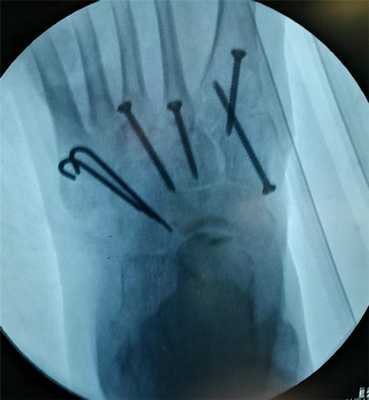

В случаях этого повреждения показано оперативное лечение, открытое устранение подвывиха основания 2 плюсневой кости с фиксацией винтом. Устранение подвывиха производится из доступа в 1 межплюсневом промежутке, рубцовая ткань и остатки связки могут интерпонировать сустав, тогда потребуется их удалить. После вправления производится предварительная фиксация спицей и рентгенологический контроль.

Затем устанавливается винт соединяющий основание 2 плюсневой кости и медиальную клиновидную кость.

В такой ситуации остаётся один выход - операция. Необходимо освободить от рубцовых тканей весь сустав Лисфранка - а это как минимум 5 предплюсне-плюсневых суставов, вернуть плюсневые кости в нормальное положение, и зафиксировать 1-2-3 предплюсне-плюсневые суставы винтами и или пластинами, а 4-5 спицами, которые через 6 недель будут удалены.

После операции целесообразно использование внешней иммобилизации - гипсовой повязки, на срок до 6 недель. Осевую нагрузку нельзя давать до 12 недель, пока не состоится артродезирование 1-2-3 плюсневых и медиальной, срединной и латеральной клиновидных костей.